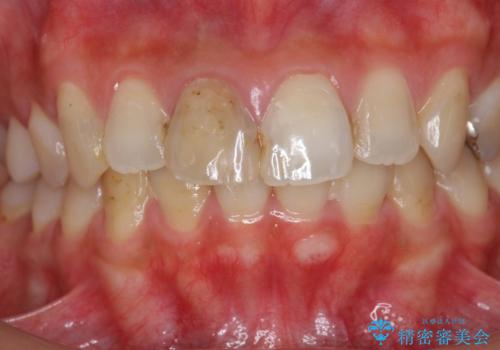

- 前歯の見た目、変色の改善を希望され来院されました。

ジルコニアクラウンによる審美性の改善を計画します。

神経の治療をした歯について

神経をとる治療を行った歯は、時間が経過すると術前のように変色し見た目を大きく損ないます。

このような場合金属を使わないジルコニアクラウンを用いた治療を行うことで天然の歯のように審美性を改善することが可能になります。